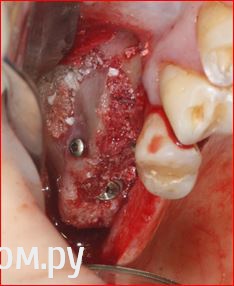

Популярный пост ILGAMSA Опубликовано 3 октября, 2014 Популярный пост Поделиться Опубликовано 3 октября, 2014 Так и не дождался фото работы с сеткой у Sahana, решил выложить свою)) http://s019.radikal.ru/i614/1410/00/65c3b52951b7.jpg http://s016.radikal.ru/i337/1410/37/25164ebcaf90.jpg http://i003.radikal.ru/1410/99/a9719eea8b2b.jpg Через 5 месяцев http://i072.radikal.ru/1410/ac/0921fe638e3d.jpg http://s02.radikal.ru/i175/1410/8b/ac9a327c900f.jpg Такие дела... 28 Ссылка на комментарий

ILGAMSA Опубликовано 3 октября, 2014 Автор Поделиться Опубликовано 3 октября, 2014 Ура! Неблоки у Ильгама ) жесткая сетка какая-то, не? Не, сетка 0,2мм, удобная.http://s58.radikal.ru/i160/1410/59/c538cd96031e.jpg как выяснилось, мостик временный давил на эту зону, отсюда подвижность сетки, графта, излишний фиброз и даже грануляции http://s017.radikal.ru/i428/1410/1e/79ddb9bb359d.jpg но на результат сильно не повлияло 4 Ссылка на комментарий

ILGAMSA Опубликовано 3 октября, 2014 Автор Поделиться Опубликовано 3 октября, 2014 здесь и синуслифт был же? там на фото перфа была на мембране или показалась?Красивый кейс!!! Спасибо))) да, синус-лифт, перфорация была. После широкого отслаивания перфа спалась. Ничем не прикрывал. 2 Ссылка на комментарий

ILGAMSA Опубликовано 3 октября, 2014 Автор Поделиться Опубликовано 3 октября, 2014 Отлично. Только двойку скосил - далековато поставил. И почему 5 месяцев, не мягковат графт?Кость плотная на двойкеДистально вряд ли лучше стало бы.Кость растет примерно на 1мм в месяц. Наращивал около 5мм Ссылка на комментарий